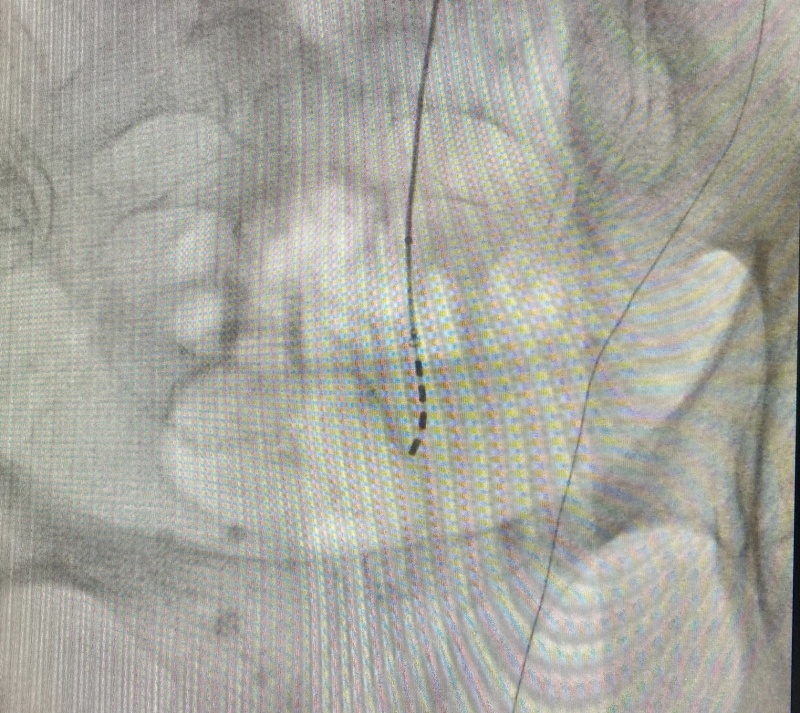

Se trata de una técnica mínimamente invasiva que consiste en la colocación de un electrodo sobre los nervios sacros encargados de transmitir las señales neurológicas que permiten el control de la evacuación urinaria y fecal. El dispositivo se implanta con anestesia local, sedación ligera y control radiológico. Su colocación no requiere ingreso hospitalario, de forma que el paciente recibe el alta apenas unas horas después del procedimiento.

Según explica Domínguez, la intervención se realiza en dos fases. En la primera, se coloca el electrodo sobre el nervio sacro y se conecta a una batería externa pegada a la piel mediante unos apósitos. De esta manera y durante unos días, como periodo de prueba, el paciente tiene la posibilidad de comprobar la eficacia del dispositivo en su domicilio, mediante la reducción de los episodios de incontinencia. Una vez se comprueba la mejoría clínica y se confirma que la terapia es adecuada, se realiza la segunda fase del procedimiento mediante la cual el electrodo se conecta a un generador subcutáneo de reducido tamaño.